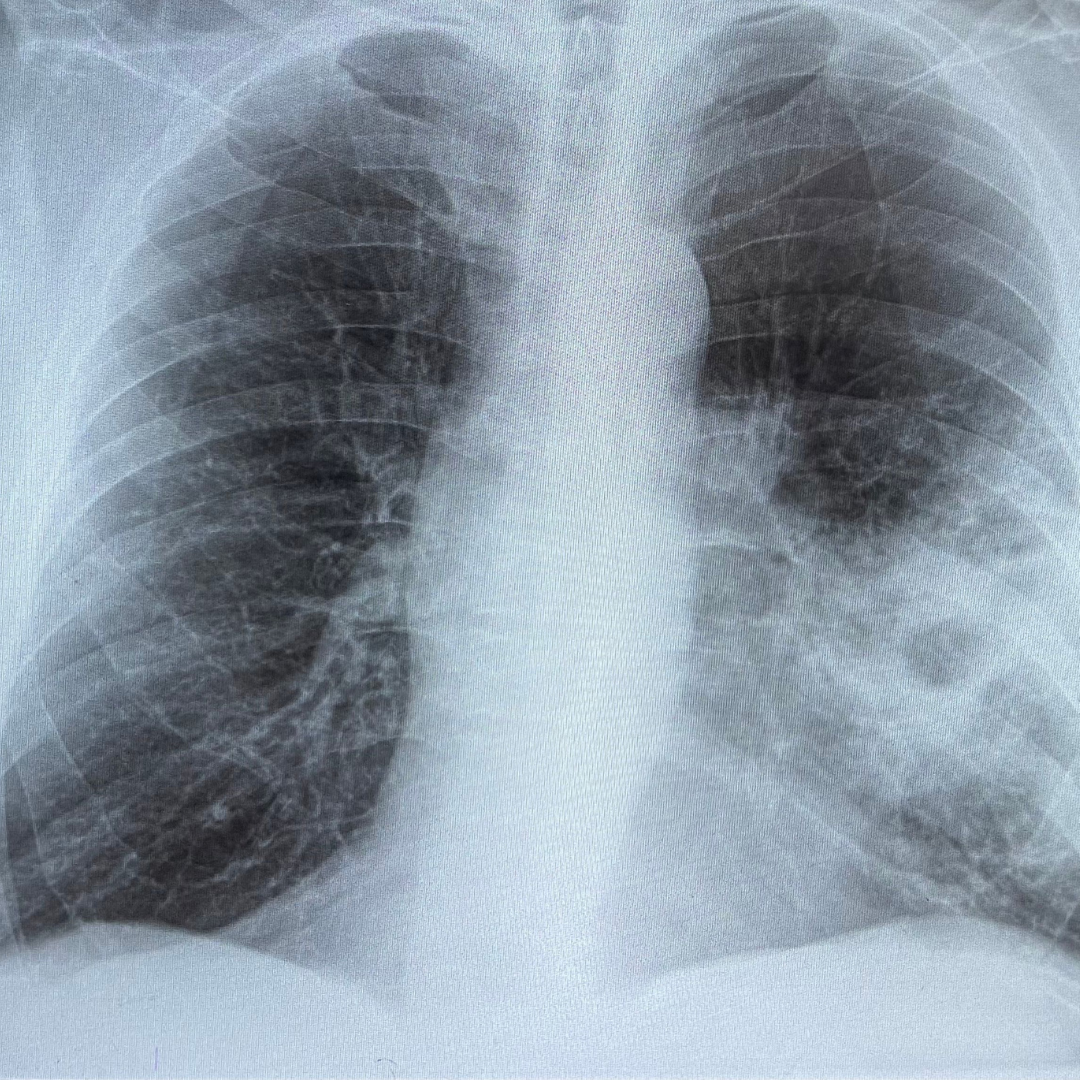

Rak pljuč je najpogostejše rakavo obolenje na svetu in glavni vzrok smrti zaradi raka v Evropi, glede na današnje številke je zaradi raka pljuč v EU do leta 2027 pričakovati kar 250.000 smrti letno. Kar tretjina obolelih z rakom pljuč  je še v »delovnih letih«, torej gre tu za dvojno izgubo – poleg človeške izgube, je tu posledično tudi ekonomska izguba.

Raziskave so pokazale, da so pri bolnikih, pri katerih je diagnoza rak pljuč ni bila odkrita v zgodnjih stadijih, možnosti preživetja izjemno nizke. Lahko rečemo, da imamo v Sloveniji veliko prednost pred drugimi evropskimi državami – namreč v Sloveniji je rak pljuč lahko izredno dobro zdravljen, še posebej, če je odkrit v zgodnejših stadijih.

Zato pazite nase in prepoznajte bolezenske znake ter reagirajte! Najpogostejši znaki in simptomi raka pljuč so kašelj (na novo nastali ali sprememba kroničnega kadilskega kašlja), hujšanje, občutek težkega dihanja, znojenje, slabša mišična moč v roki, izkašljevanje krvi, bolečina v prsih, vratu ali v ramah, hripavost, težko požiranje. Rak pljuč lahko povzroči tudi pljučnico. Rak zgornjega režnja pljuč lahko vrašča v simpatični živčni sistem ter povzroči spremembe v znojenju in prilagoditvi oči ter slabšo mišično moč v roki.

Rak pljuč se zdravi kirurško, s kemoterapijo, obsevanjem, tarčnimi zdravili ali kombinacijo različnih zdravljenj. Ustrezna terapija se izbere glede na tip raka, njegovo razširjenost in splošno stanje bolnika.